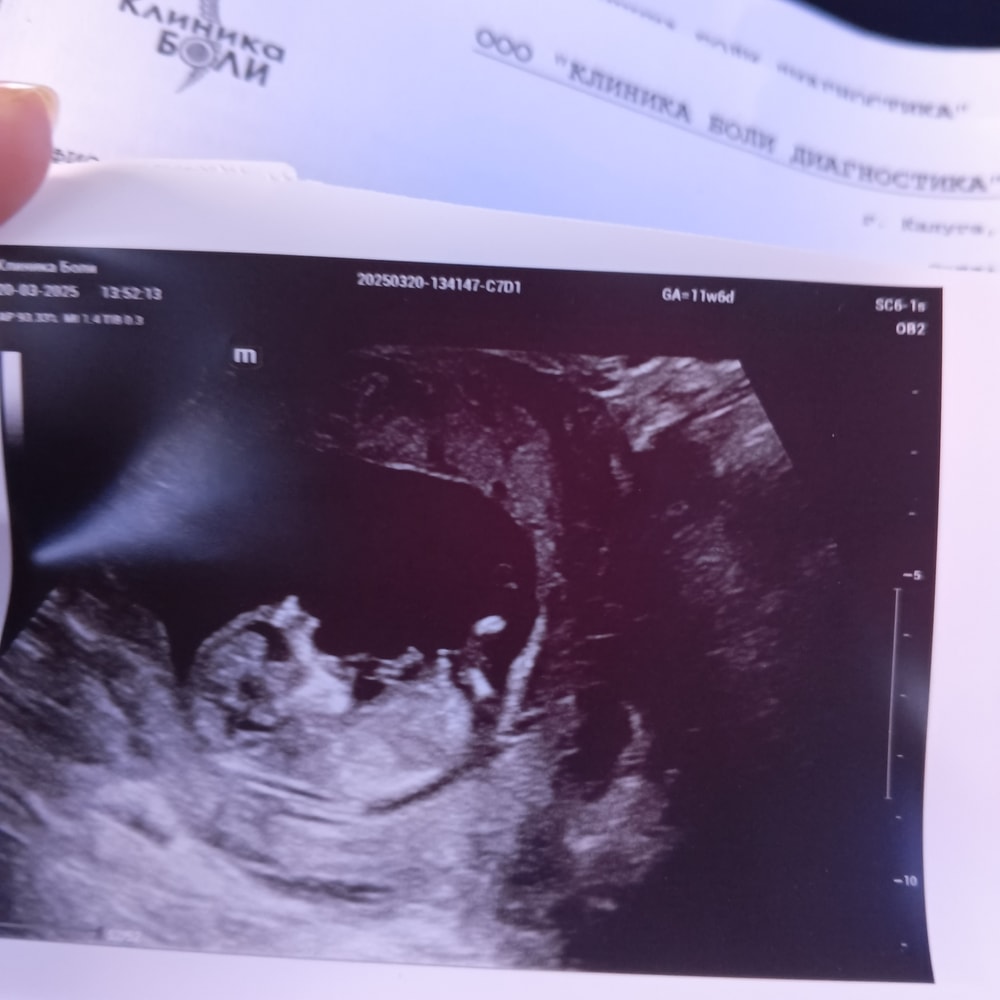

Алина, ого впервые такое слышу про полосочку и шарик. А тут что видите? Изображение

Светлана , какой здесь срок?

Алина, 12 и 4

Светлана , вот визуализация не очень. Чтоб понять надо видеть очень четко, желательно на видео. А вообще бугорки очень коварные. Я недавно видела бугорок, но точно б сказала, что это мальчишка, он вверх смотрел. А оказалась девочка

Наталья, да по поводу наклона я знаю, но я не понимаю, где на моих фото узи половой бугорок, чтобы посмотреть наклон😀 У многих половой бугорок виден наглядно, а у меня нет) Вот на этой фото прям наглядно видно половой бугорок и это девочка подтвержденная) Изображение